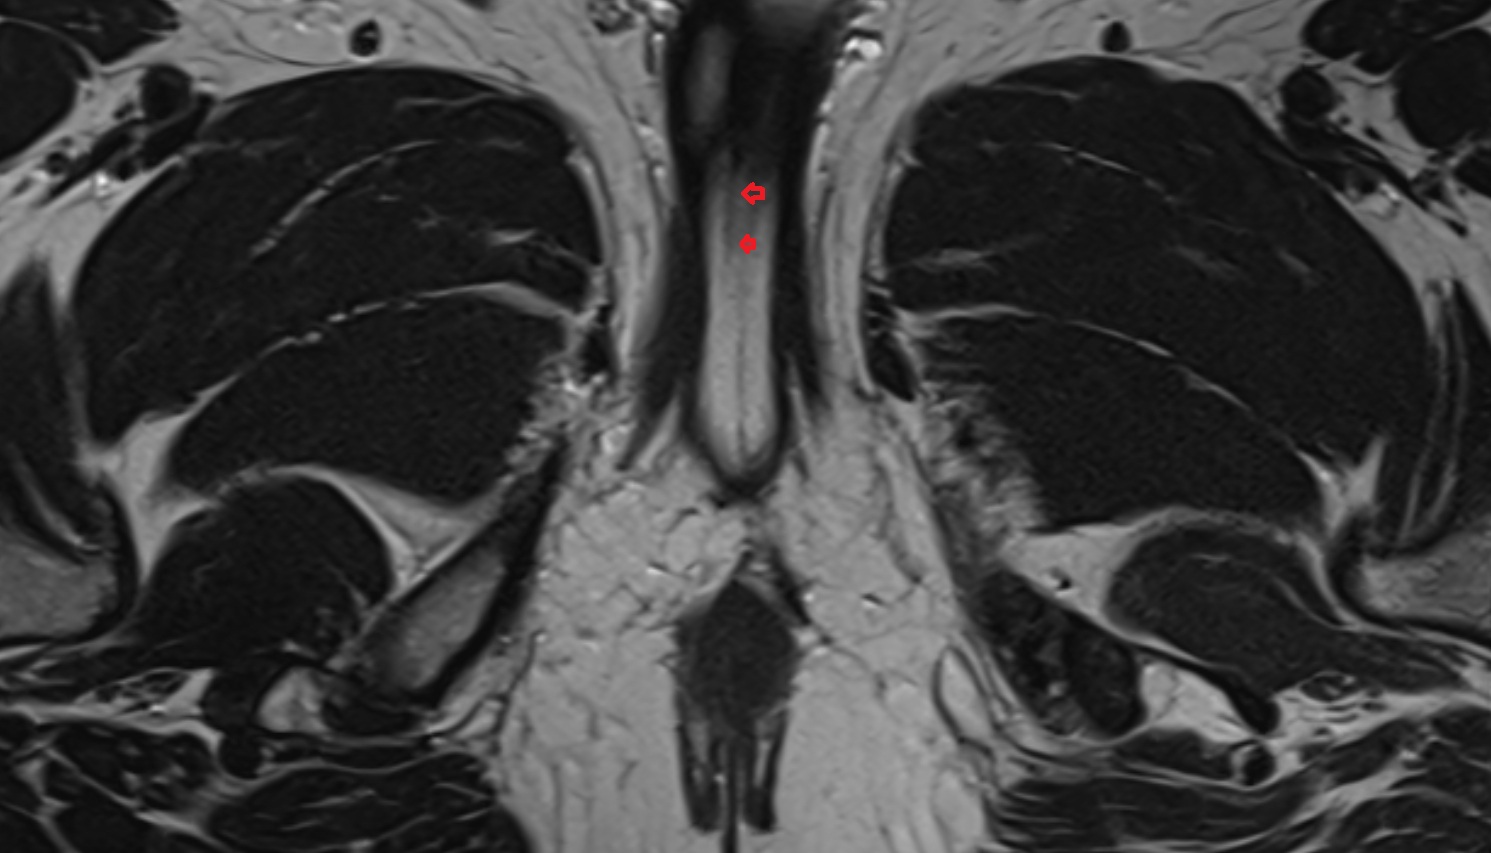

- Pituitary stalk

- Pituitary gland

- Anterior lobe of pituitary gland

- Posterior lobe pituitary gland